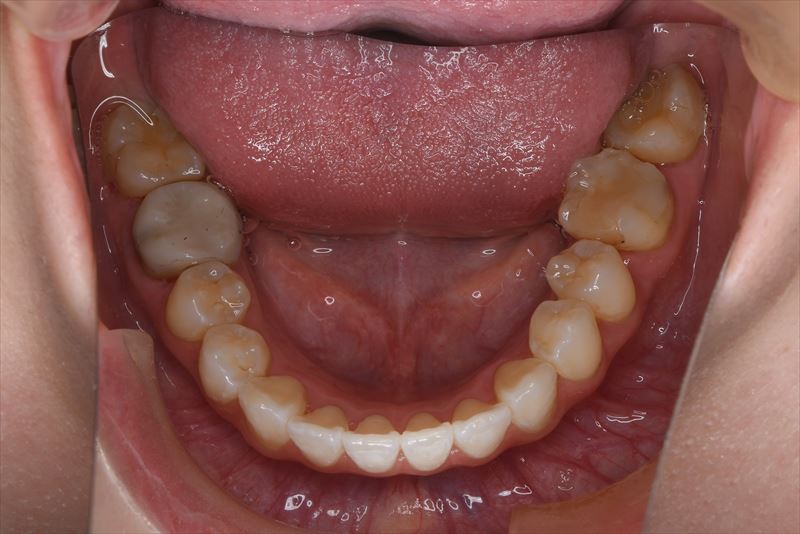

治療後

- 1年3か月、21回

- 上顎左側6番は失活歯で根尖病巣を認めたため抜歯し、上顎左側8番を代わりに使用することとしました。アンカースクリューを使用することにより、健康な歯を抜歯せず臼歯の遠心移動で叢生の改善できました。治療期間が短かく良好な咬合を獲得できました。